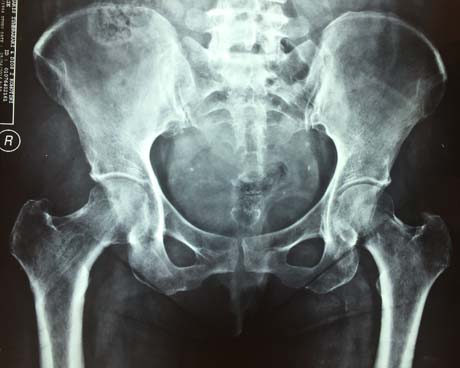

Post-op X-ray of the right hip

Hip X-ray 5 months post-op